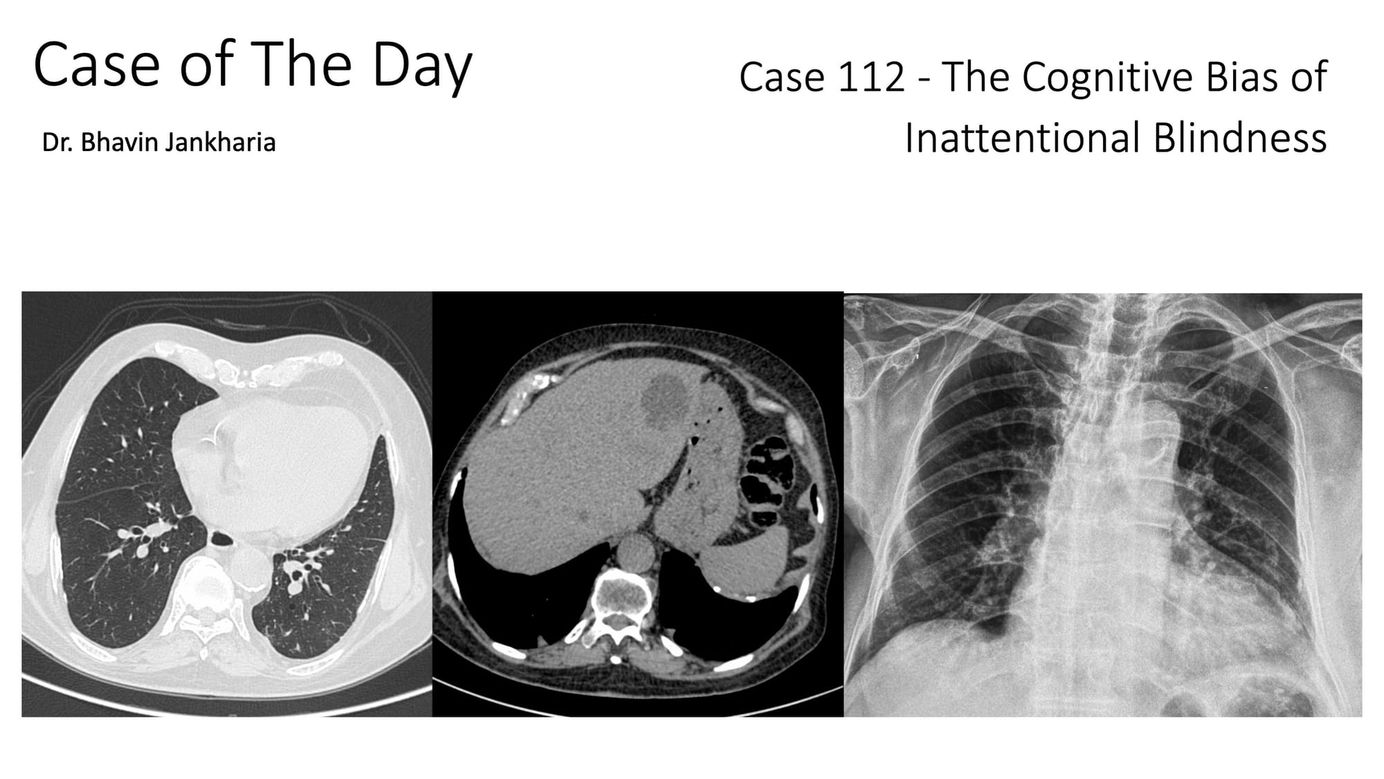

Case of the Day 112 - The Cognitive Bias of Inattentional Blindness Members Public

We need to up our game and pick up all the findings that exist by paying attention to different parts of the chest, scrolling slow and fast and asking ourselves each time whether every area is normal or not